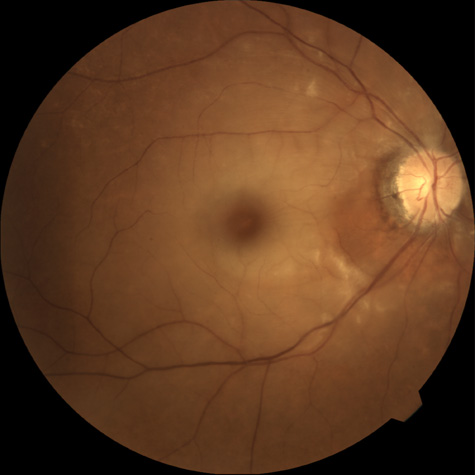

The clinical picture is typically striking. Patients present with a sudden painless loss of vision. The appearance of a cherry-red spot in the fundus is characteristic (Fig. 1).2 The cherry-red spot appears because soon after obstruction of the blood flow to the inner retina, the normally transparent retina becomes opaque and blocks the brownish-red color from the underlying choroid, which is still supplied by blood. Because the retina overlying the foveola is relatively thin, however, the normal color of the choroid is still visible in this area.3,4 Although characteristic, the cherry-red spot is not pathognomonic for central retina artery obstruction.5 Sometimes the characteristic cherry-red spot does not develop; there may be only a slight accentuation of the brownish-red color in the foveola.4 It is not known how long it takes this cherry-red spot to appear, but in a primate model, it has appeared as early as 30 minutes after obstruction.6 An afferent pupil defect is usually present.2

Fig. 1. A: Acute central retinal artery obstruction with a cherry-red spot. B and C: Intravenous fluorescein angiography. There is a delay of dye appearance in the central retinal artery, and when it does appear, it does not fill the arteries completely. D: Ocular coherence tomography (OCT) at the time of occlusion showing the increase in retinal thickness and reflectivity of the inner layers of the retina. E: Seven months later there is significant optic atrophy(G), and the OCT (F) shown now has marked thinning of the retina.

With time, the retinal opacity diminishes, generally leaving an optic nerve that is atrophic (Fig. 1). Frequently, thinned retinal arteries and veins also remain.7,8 No foveolar light reflex is evident, and a finely pigmented appearance of the macula is typical.7 In some cases, arterial collaterals develop at the optic disc.9–11 Rarely, anatomoses that exist between the central retinal artery and the ciliary arteries become visible as preretinal loops (Nettleship collaterals) after an occlusion at the edge of the disc.12,13,378In approximately 20% of patients, an embolus is evident somewhere in the arterial system.14 Emboli are discussed later.

Intravenous fluorescein angiography is useful in showing the details of the abnormal circulation of a central retinal artery obstruction (Fig. 1). The principal abnormality is the delay in the appearance of the dye in the central retinal artery and its branches.2 Rather than the central retinal artery and its branches filling rapidly, considerable time may elapse before the entire arterial system is filled.15 The filling of the retinal arteries is often abnormal, with the fluorescein partially filling an artery (a dye front) or hugging the vessel wall, as in normal venous filling.15

Optic coherence tomography (OCT) of an acute central retinal artery occlusion shows a slight increase in the thickening of the retina and reflectivity of the inner layers of the retina that correspond to the opacity seen clinically (Fig. 1).409 With time, the disc becomes atrophic and the retina thinner.